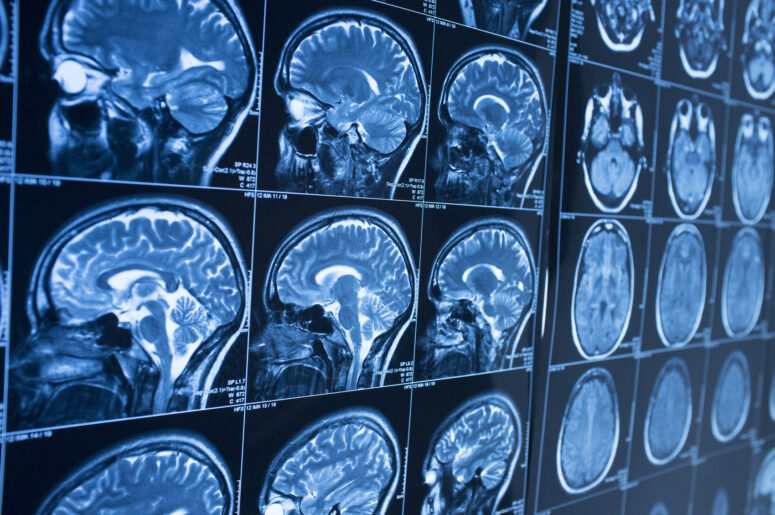

When someone sustains a concussion, it is typically because a forceful jolt or blow to the head has caused their brain to hit the interior of their skull. This type of impact often results in bruising, which in turn causes the injured party to display a varying set of symptoms.

A concussion is a form of mild traumatic brain injury (TBI). In this context, the designator of “mild” is extremely misleading. All brain injuries should be taken seriously and treated by a medical professional. There are too many variables in play to leave things to chance, and the consequences could be worse if left untreated.